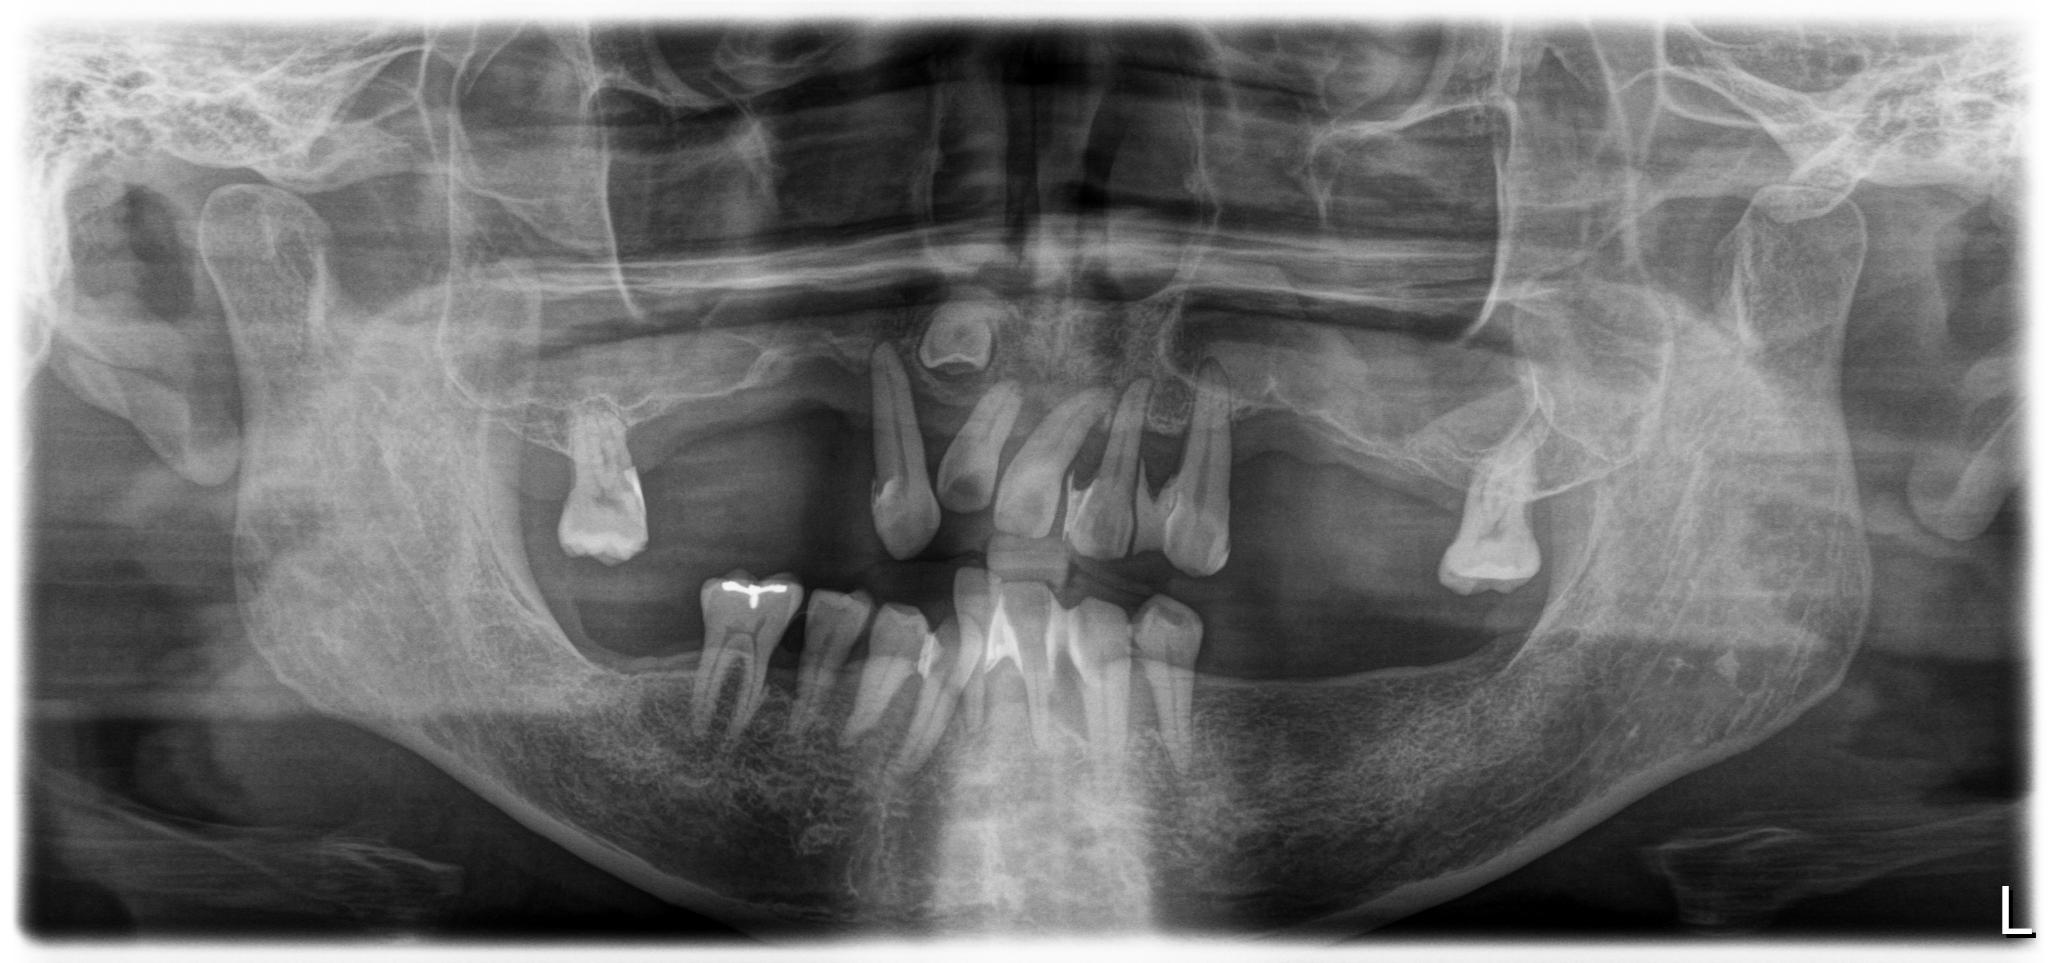

術前

上下総義歯を使用していましたが、食事や会話の度に歯茎に痛みが生じ、日常生活において多大なストレスを抱えていました。情報誌「グランザ」でこちらのクリニックを知り、義歯の悩みから解放されたいという切実な思いから相談に行くことに決めました。

過去に麻酔による全身痙攣の経験があることや骨粗鬆症の治療薬を服用中であることなど外科的処置に対するリスク要因を持ち合わせていました。ですが、丁寧なカウンセリングと説明を受け、取り外し不要な「固定式の歯」を得られることへの魅力が不安を上回り、手術をうけることにしました。